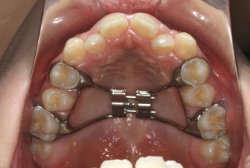

混合歯列期から治療開始した側方拡大による非抜歯症例

「配列の凸凹を治したい」という主訴で来院したケースです。診断の結果、永久歯がすべて生えそろうと、かなり厳しい叢生(歯並びの凸凹のことです)になる可能性が高いと判明しました。原因としては特に上の顎の骨が小さいため、歯を収容する容量不足になっていると診断しました。このケースの場合は、成長発育期に治療開始しますので、顎の骨を土台ごと大きくすることが可能です。

そこで、まず急速拡大装置を使用して上顎骨の拡大を行い、上顎骨の容量が拡大したことを確認後、マルチブラケット装置を使って全体の修正をする、と言う二段階の作戦をとることになりました。

この時期に使う急速拡大装置は、適切な診断に基づいて正しく使用することで確実に骨を大きくすることができます。拡大することで隙間が確保できるので、永久歯の抜歯を避けることができます。

急速拡大装置を1日1回装置の中央にある拡大ネジを、ご自身で回して頂くことで25日間くらいかけて、6mmほど拡大しました。拡大後は、上顎の前歯の隙間が広がっていることがお分かりいただけると思うのですが、土台の骨ごと広がるのでこのような隙間ができます。その後1年半くらいマルチブラケット装置を使用して、全体の修正を行いました。

結局、歯の本数を減らすことなく、すべてご自分の歯を残して正しい配列にすることができました。このケースの場合、2009年10月より拡大と経過観察を行い、2012年3月より1年2ヶ月マルチブラケット装置を装着、2013年5月に治療を終了しました。2段階で行う治療としては短期間で終了しているケースと思います。